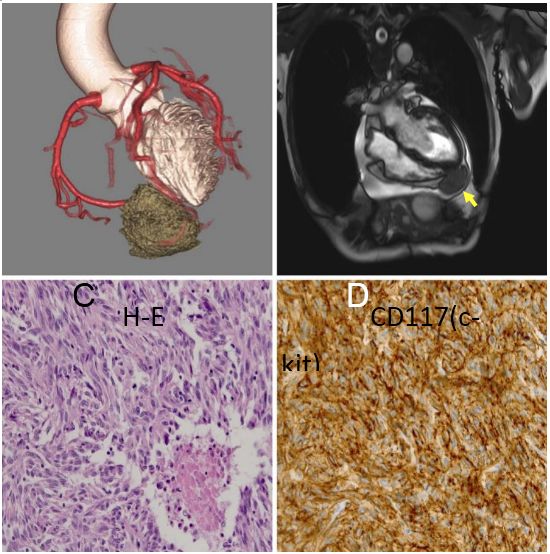

背景介绍:一个89岁的日本男子吐血带来我们医院。增强CT显示胃和胰腺之间的11×10×10厘米*小单大**房性囊性肿瘤(图A,箭头)。胃镜检查:发现一个大在胃体上部大弯的软凸起,凸起表明面有一个易碎的溃疡(图B)。病人入院后12天接受胃部分切除术。组织学上,被切除的标本被发现是囊性病变并有部分钙化(图片C)。囊肿包括浆液和血液,病理分析为梭形细胞成分,且c-kit和CD34免疫组化阳性(图片D)。有丝分裂率为10/50个高倍视野,根据弗莱彻的危险分级诊断为胃肠道间质瘤(1)。大多数胃肠道间质瘤为实性肿瘤,囊性改变少见(2)。这种情况下囊性改变可能是由于肿瘤的快速生长和坏死引起的。这种情况下囊性改变可能是由肿瘤的快速生长和坏死引起的。胃肠道间质瘤表现为单房性囊性病变,虽然罕见,应于上腹部囊性病变的鉴别诊断。